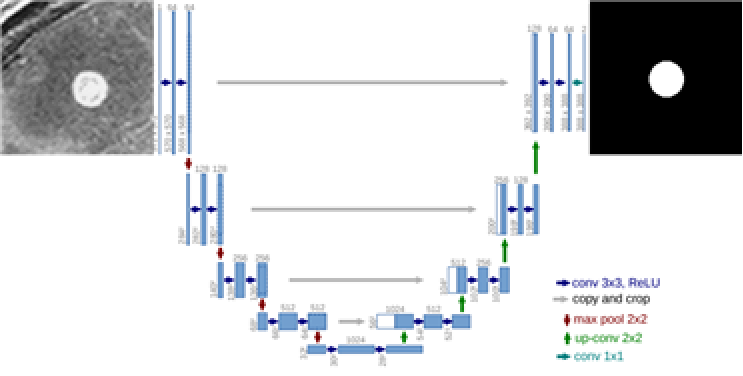

AI 모델 상세 설명서 다운로드 AI 모델 다운로드학습 알고리즘 RetinaNet 및 U-net 기반

RetinaNet과 U-Net을 함께 사용 또는 U-Net만 사용

U-net network 개념도

학습 조건 epoch: 500

batch: 128

optimizer: Adam

loss: categorical cross-entropy, focal-loss

iteration: 4,434